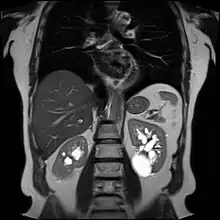

![]() | |

| Renal cyst of the left kidney (hyperintense area) as shown on MRI. | |

Numerous renal cysts are seen in the cystic kidney diseases, which include polycystic kidney disease and medullary sponge kidney.